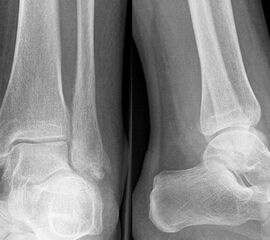

Die Standard-Röntgenaufnahmen des oberen Sprunggelenks bestehen aus drei Aufnahmen: der antero-posterioren Aufnahme (ap), der antero-posterioren Aufnahme mit Innenrotation des Unterschenkels von 20° („Mortise view“), sowie der streng seitlichen Aufnahme (siehe S2-Leitlinie Sprunggelenksfraktur). In der Röntgen-Bildgebung sollte neben den klassischen Frakturzeichen die Integrität der Syndesmose beurteilt werden. Dies erfolgt über die Beurteilung der Breite des lateralen und medialen Gelenkspalts („medial clear space“), des tibiofibularen Abstands 1cm oberhalb des OSG-Gelenkspalts („tibiofibular clear space“), bzw. der tibiofibularen Überlappung. Eine Verbreiterung des tibiofibularen Abstands über 5 mm oder die Erweiterung des medialen Gelenkspalts können Zeichen einer begleitenden Syndesmosenverletzung sein. (Abbildung 3) 6.

Liegt eine Fraktur des oberen Sprunggelenks vor, ist sowohl zur Entscheidung für ein konservatives oder operatives Vorgehen, als auch zur Operationsplanung, ein ausreichendes Verständnis der Fraktur und ihrer Morphologie notwendig. Insbesondere bei komplexen Verletzungen ist dafür die konventionelle Röntgenaufnahme in vielen Fällen nicht ausreichend. So konnten z.B. Black et al. zeigen, dass die operative Strategie zur Versorgung von OSG-Frakturen in 24% basierend auf einer zusätzlichen CT-Bildgebung relevant geändert wurden 7. Dies betraf die Lagerung, die Wahl des Zuganges und die Art der osteosynthetischen Versorgung. Besonders häufig änderte sich das Vorgehen bei Verletzungen des medialen (21%) und des posterioren Malleolus (15%). Darüber hinaus führten dislozierte (dislozierte Frakturen 31% vs. nicht-dislozierte Frakturen 20%) oder komplexe Frakturen (Trimalleolar-Frakturen 29% vs. Unimalleolar-Frakturen 10%) besonders häufig zu relevanten Änderungen des operativen Vorgehens. Die Computertomographie ist daher, insbesondere bei Bi- und Trimalleolar-Frakturen, essentiell für das Verständnis der Fraktur und somit für die Planung und Durchführung der Operation. In Abbildung 4 und 5 sind exemplarisch ein Röntgen- und ein CT Befund gegenübergestellt.